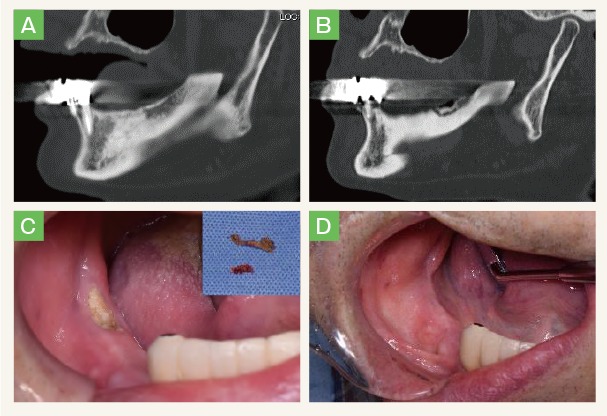

- 初診時CT斜位像で右側下顎体部には骨硬化性変化が認められる。

- 初診から1年6か月では腐骨の分離が認められる。

- 初診から1年7か月。初診時よりも露出骨の範囲は拡大しているが、排膿や周囲に感染所見は認めない。局所麻酔下に腐骨除去術を施行。右上に除去した腐骨を示す。

- 術後1か月。骨露出は認めない。